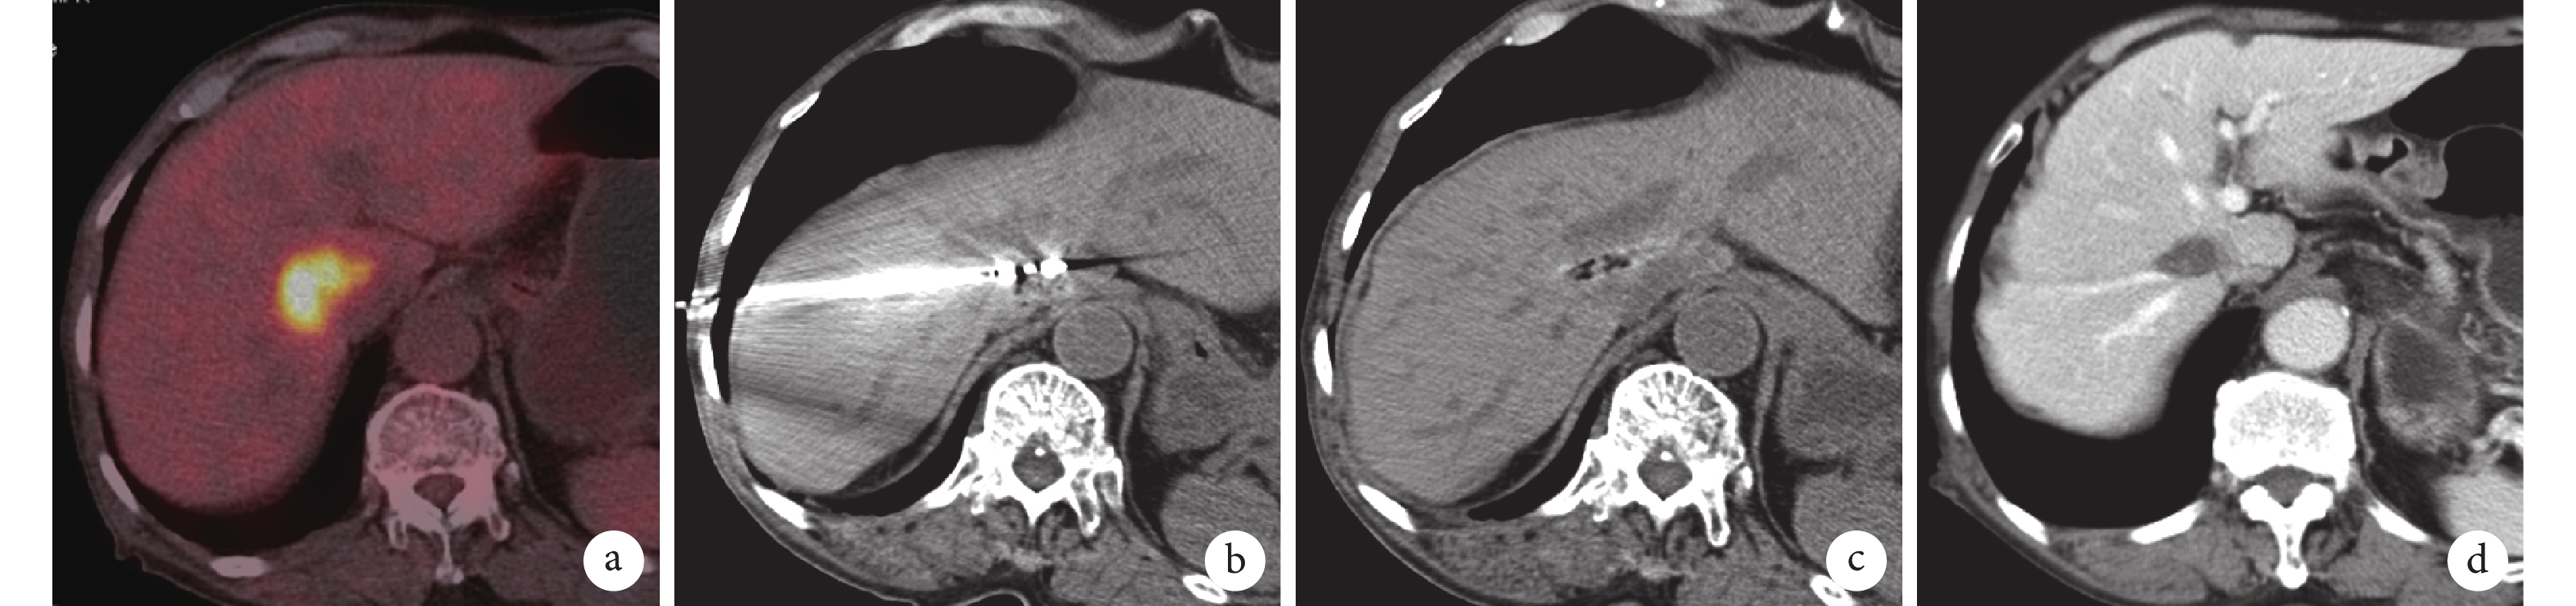

患者86歲,男,2018年7月20日因“院外診斷乙狀結腸癌伴孤立性肝轉移”入我院,外院PET/CT檢查結果見圖4a。入院后 5 d行腹腔鏡乙狀結腸癌切除術(術后病理診斷為中分化腺癌、腸周淋巴結轉移),術后15 d在全身麻醉下行CT引導下經皮穿刺肝S9段轉移癌微波消融術,術中見肝S9c及S9d段交界區約4.0 cm×2.9 cm大的混雜低密度灶,選擇右后入路使消融針沿腫瘤最長徑線平行,并穿透腫瘤最大徑線(圖4b),消融結束后CT掃描見腫瘤縮小并完全消融(圖4c)。消融術后50個月因腦梗死住院治療,目前處于腦梗死治療恢復期。消融術后55個月全身復查,CT檢查提示無肝臟腫瘤復發(圖4d)及全身轉移,目前總生存期已經超過56個月,患者已經91歲,繼續隨訪。

a:PET/CT檢查示肝S9d、S9c段交界區高代謝灶,考慮肝轉移癌;b:肝S9段轉移癌消融術中,消融針穿透病灶最長徑線;c:消融結束,轉移癌消失,術區未見殘留;d:術后55個月復查,肝臟術區無復發

本例患者初診時乙狀結腸癌同時性肝臟S9d段寡轉移,屬于晚期。患者全身情況尚好,家屬不愿意放棄,在MDT診療模式下討論決定治療方案[12]:相對微創的腹腔鏡下乙狀結腸癌切除、分期處理肝臟S9段寡轉移病變。患者腸癌術后恢復順利,但年齡高達86歲,不適合化療,肝臟病變切除難度及風險更大,所以筆者團隊嘗試了CT引導下的肝臟S9d段轉移癌精準微創消融術,手術及術后恢復順利,近期療效評價完全消融,在未做其他任何綜合治療的情況下,暫未見局部復發及遠處轉移。